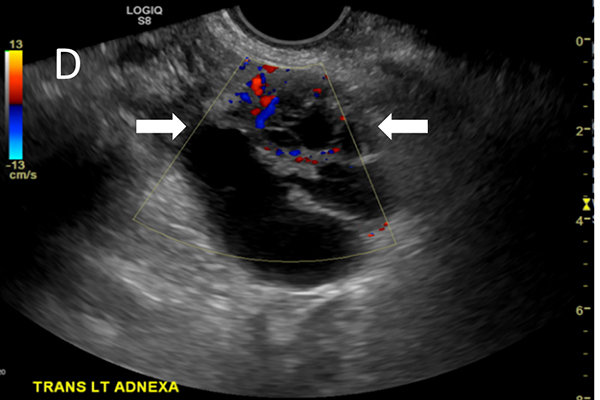

The study will include two groups of women: those at risk for ovarian cancer due to a suspicious ovarian mass or family history, as well as women who have a deleterious mutation of the ovarian cancer genes, for example, the BRCA1 and BRCA2 mutations, shown to have a high risk of breast and ovarian cancers. The standard of care for women at high risk for ovarian cancer had traditionally been regular transvaginal ultrasound every six months and blood tests for the cancer antigen CA 125. However, ultrasound is not very effective at identifying early-stage disease, and CA 125 is not specific because some patients who have ovarian cancer may not have increased CA 125 levels.

The study stems from positive results in a 2017-2018 pilot study when Zhu and the team tested the co-registered PAT/US. She and members of her lab created a sheath with optical fibers that wraps around a standard transvaginal ultrasound probe used to take images of ovaries suspected to be cancerous. The light from the laser propagates, gets absorbed by the tumor and generates sound waves, revealing information about the tumor vasculature and blood oxygen saturation (sO2) inside the ovaries made visible by the ultrasound. In the pilot study, the PAT/US technology identified invasive ovarian cancers based on higher levels of relative total hemoglobin (rHbT) and lower sO2 than benign and normal ovaries.

In the new study, Zhu and her team will use the PAT/US technology to get a detailed look at the blood vessels and sO2 in the ovaries of about 250 patients at the School of Medicine and Barnes-Jewish Hospital who are at risk for ovarian cancer or have the deleterious genetic mutation in one of the ovarian cancer genes. The team will enroll women who are within a few months of having surgery to remove their ovaries and high-risk women who have risk-reduction surgery within two years. For high-risk patients, the team will follow the patients every six months for up to two years to evaluate the ovarian lesion vasculature and sO2 changes to determine if the PAT/US can be used as an effective screening tool for early detection of ovarian cancer. The radiology and gynecology clinical trial offices will work together on patient recruiting and regulatory support.